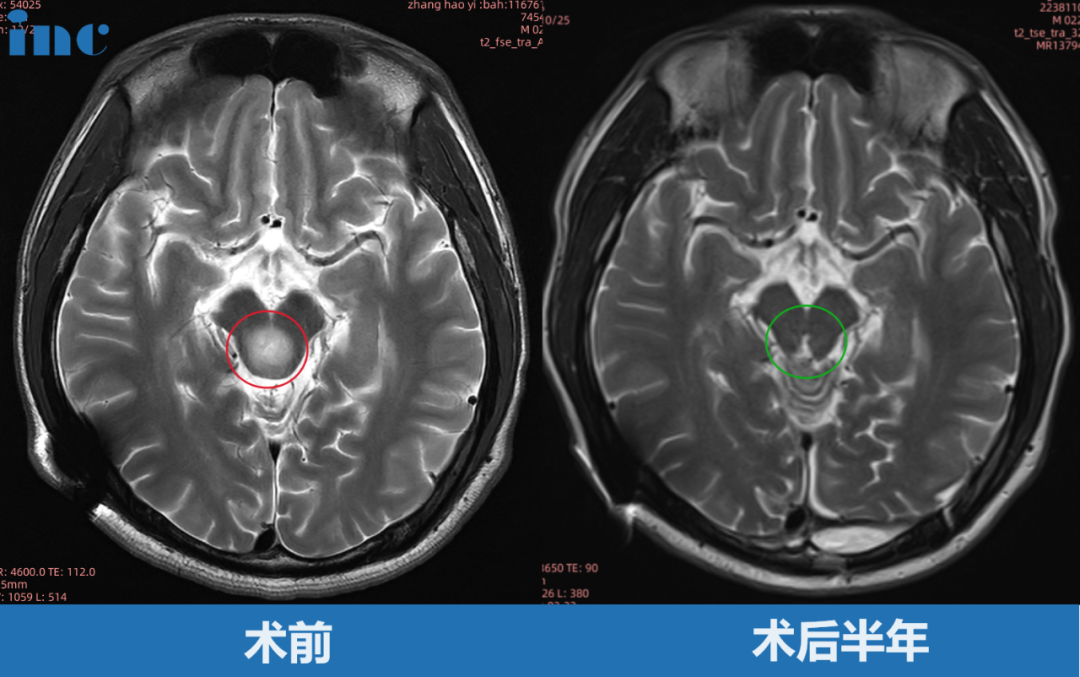

小远因突然出现的剧烈头痛伴呕吐症状,于当地医院就医检查,提示中脑顶盖占位性病变,最大直径约8mm,随后一年磁共振复查无变化。2年会复查磁共振提示肿瘤增大,最大直径 12mm。2月后复查核磁再次提示肿瘤增大,自行测量肿瘤大小约 18mm,两月内竟激增6mm!经巴教授主刀后,肿瘤全切。